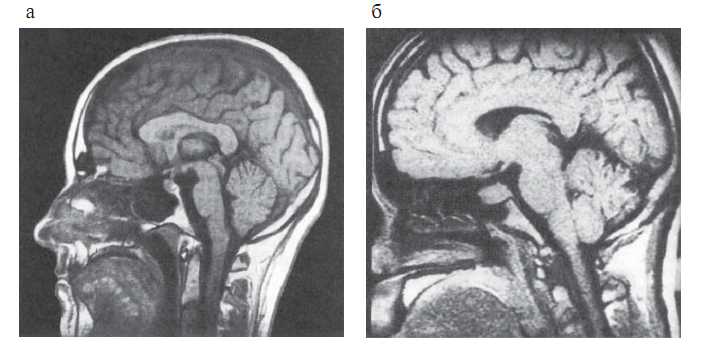

Гипофиз бен гипоталамусты визуализациялау әдісі ретінде, сонымен қатар гипоталамус-гипофизарлы аймақтағы түзілістердің топикалық диагностикасы мақсатында МРТ қолданылады (2.4сурет). МРТ гипофизде дамыған азғантай өзгерістердің өзін, ісіктердің, кисталардың, қан құйылулардың кистозды компоненттерін анықтауға мүмкіндік береді. МРТ-да сүйек тіндері мен түрлі тұздардың шөгуі анықталмайды.

Сурет 2.4. Гипоталамус-гипофиз аймағының магнитті-резонансты томографиясы

а — қалыпты жағдайда (сагиттальды проекция);

б — гипофиз макроаденомасы (сагиттальды проекция)

Контрасты заттарды қолдану МРТ-ның диагностикалық мүмкіндіктерін арттырады. МРТ-ның негізгі артықшылығы- сәулелік жүктеменің болмауы, яғни науқасты бірнеше рет динамикалық бақылау мүмкіндігінің болуында.